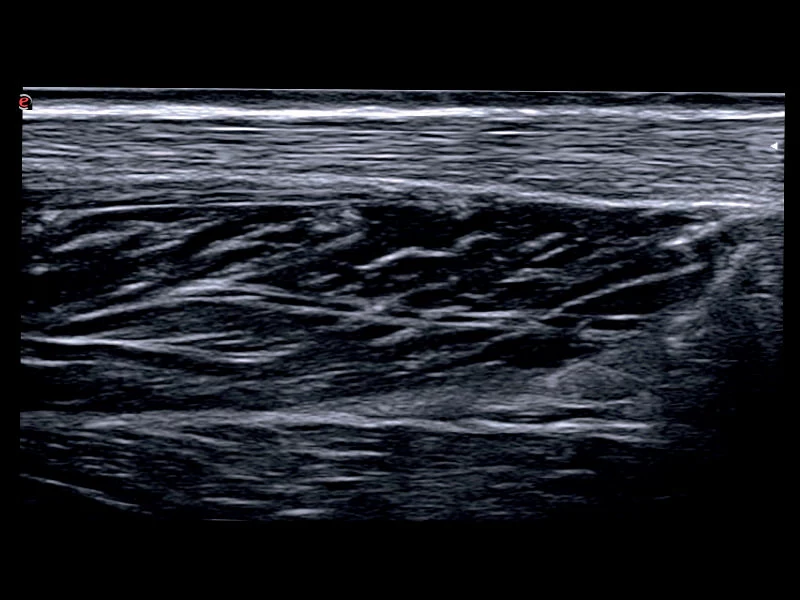

MyLab™C30 - MSK nerve

MyLab™C30 - MSK nerve